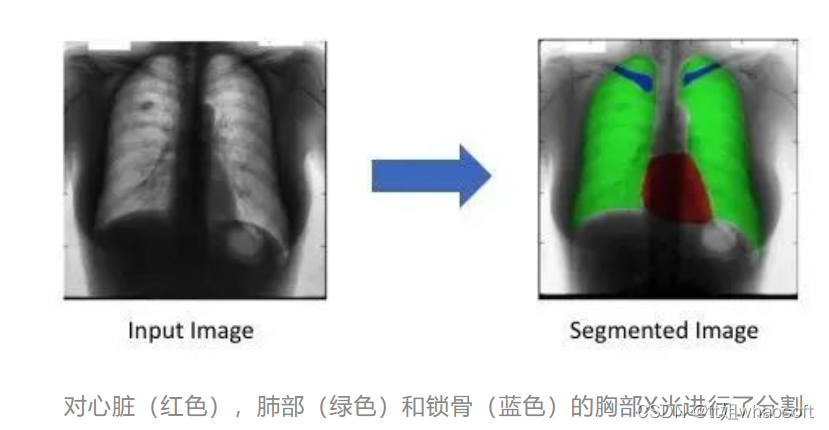

什么是物体检测? 给定一张图像,我们人类可以识别图像中的物体。例如,我们可以检测图像中是否有汽车,树木,人等。如果我们可以分析图像并检测物体,我们可以教机器做同样的事情吗?答案是肯定的。随着深度学习和计算机视觉的兴起,我们可以实现目标检测的自动化。我们可以建立深度学习和计算机视觉模型,可以检测和定位目标,计算它们之间的距离,预测它们的未来的位置等。目标检测在计算机视觉和机器学习中有着广泛的应用。目标跟踪、闭路电视监控、人类活动识别,甚至自动驾驶汽车都利用了这项技术。为了更好地理解它,考虑下面的图片。

图中为一幅道路交通图像从车辆上看的目标检测。这里我们可以看到它正在检测其他车辆,交通信号等。如果车辆是自动驾驶汽车,应该能够检测到行驶路径、其他车辆、行人、交通信号等,以便平稳、安全驾驶。现在我们已经了解了目标检测,让我们转移到一个稍微高级的技术,称为图像分割。通过分析下图,我们可以很容易地理解目标检测和图像分割之间的区别。

图2,目标检测和图像分割

这两种方法都试图识别和定位图像中的物体。在目标检测中,这是通过边界框实现的。该算法或模型将通过在目标周围绘制一个矩形边界框来定位目标。在图像分割中,对图像中的每个像素进行标注。这意味着,给定一幅图像,分割模型试图通过将图像的所有像素分类成有意义的对象类别来进行像素级分类。这也被称为密集预测,因为它通过识别和理解每个像素属于什么对象来预测每个像素的含义。“图像分割的返回格式称为掩码:一个与原始图像大小相同的图像,但对于每个像素,它只有一个布尔值指示目标是否存在。“我们将在本案例研究中使用这种技术。现在我们有了目标检测和图像分割的概念。让我们进一步理解问题陈述。